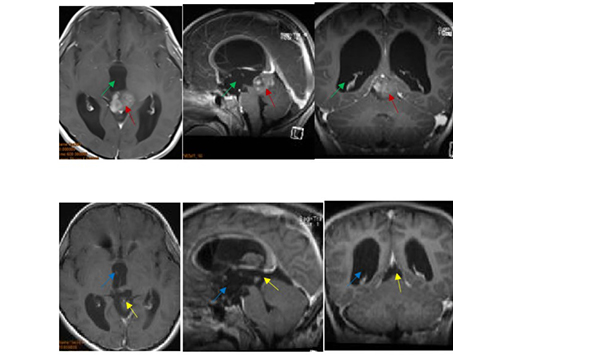

8歲小患者經(jīng)德國巴特朗菲教授術(shù)前術(shù)后影像對比

對于松果體區(qū)患者來說,手術(shù)治療的入路一般包括幕下小腦上入路、枕下小腦幕入路、后縱裂經(jīng)胼胝體入路等,而更佳的手術(shù)治療方式主要依賴于腫瘤解剖學特點的不同。針對8歲小患者這個病例,巴特朗菲教授采取的是幕下小腦上入路結(jié)合幕上枕下乙狀竇旁經(jīng)小腦幕入路,較終腫瘤得以全切除,且盡力減少了組織的損傷,這對預防后期腫瘤的復發(fā)起到了較大作用。